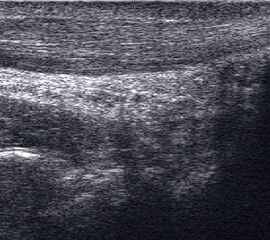

Peronealsehnenläsion

Lagerung: Rückenlage, Innendrehung des Beines

Schnittführung: TS und LS hinter dem Außenknöchel beginnen und die beiden Peronäalsehnen bis zur Basis des Metatarsale V durchmustern, für Longus-Sehne auch plantare Untersuchung in TS und LS (Abb. 39).

Referenzstrukturen: Fibulahinterkante, Basis Metatarsale V.

Befunde: Halophänomen und echoarme Verdickung bei akuter Tendinopathie, zunehmend inhomogen und echogen bis hin zu Teilrupturen bei chronischem Verlauf. Für die Erkennung von Teilrupturen sind TS in verschiedener Höhe besonders wichtig. Bei komplettem Riss zeigt sich der Sehnenstumpf wie eine Spargelspitze (Abb. 40). Der retrahierte Sehnenstumpf ist von Flüssigkeit und Hämatom umgeben.